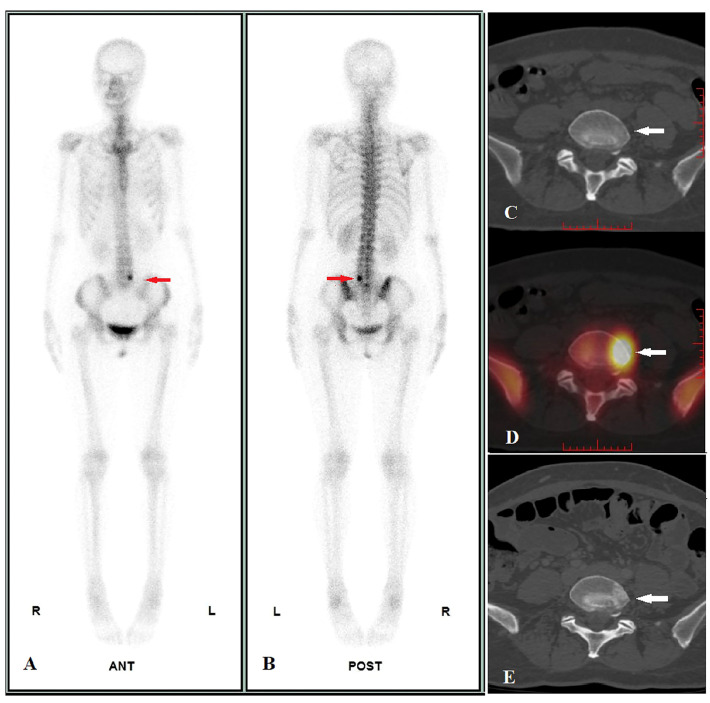

Donna di 47 anni con carcinoma neuroendocrino polmonare in stadiazione pre-trattamento.

L’imaging funzionale ha rilevato una chiara ipercaptazione patologica alla vertebra L5, caratterizzata da un elevato valore quantitativo (SUVmax = 45.41). Tuttavia, l’imaging morfologico (TC) iniziale era completamente negativo, non mostrando alterazioni strutturali dell’osso (C).

A distanza di tempo, l’esame TC di controllo ha documentato l’insorgenza di reazione osteoblastica (sclerosi) esattamente nello stesso punto segnalato dalla SPECT/TC mesi prima (E).

Questo caso “vero positivo” dimostra l’eccellente sensibilità dell’imaging scintigrafico (e in particolare della SPECT/TC quantitativa) nell’identificare micrometastasi o lesioni ossee in fase estremamente precoce, con largo anticipo rispetto alla comparsa dei segni morfologici visibili alla radiologia tradizionale.